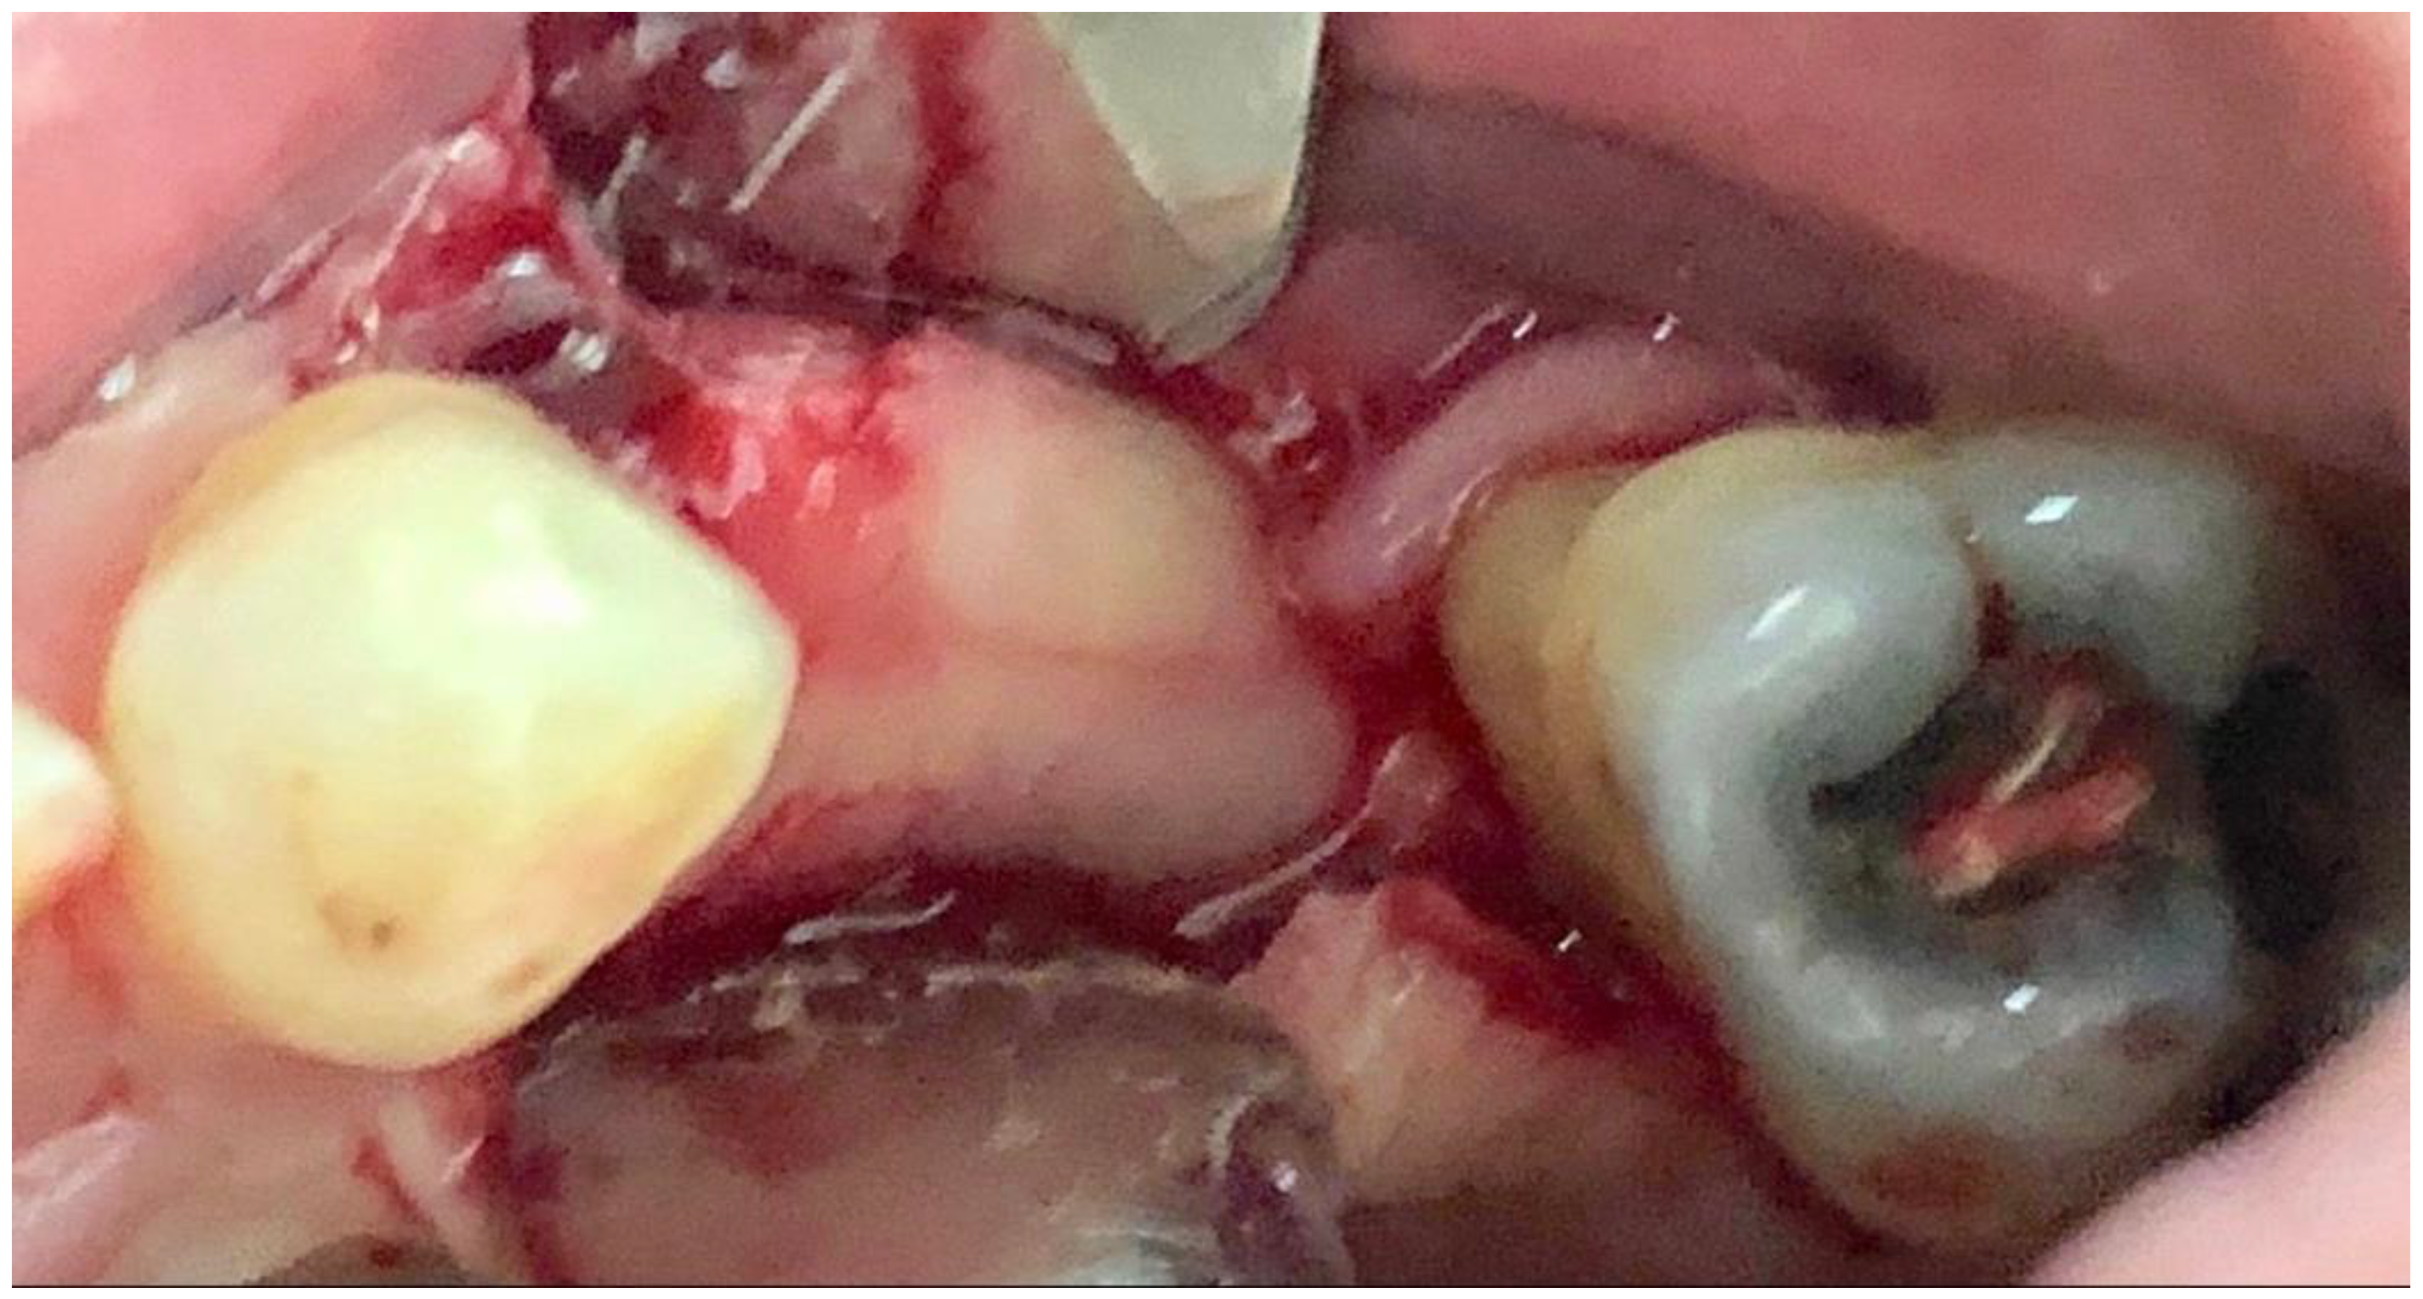

3.3. Case 3

A 43-year-old male patient had a motorcycle accident and traumatically lost teeth 11 and 12. After a period of soft tissue healing the area was operated on in order to place two dental implants to replace the missing teeth (Figure 13 and Figure 14).

Figure 13.

The edentulous area showed some healing at the site of 12 but still a deep dehiscence on 11.

Figure 14.

Two implants in place of the one on 11 with several threads exposed.